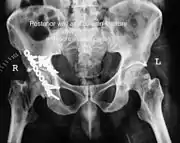

| Acetabular fracture as seen on plain X-ray |

| Posterior wall | This is the most common variety of acetabular fracture. It typically occurs due to dashboard injury; when a person travelling in a vehicle involved in a head-on collision, the force applied over the flexed knee travels along the femur bone to the head of the femur, breaking the posterior wall of the acetabulum. The head of the femur is dislocated outside the joint. | T shape | When a transverse fracture also had a vertical fracture line, it is called a T shape fracture. Here the innominate bone is broken in such a way that all three parts of it, the ilium, the ischium and the pubis are separated from one another. This is a three part fracture. Though both columns are broken, the weight bearing dome is still attached to the main part of the ilium and hence it is not a true fracture of both columns.

- Posterior wall fracture: Iliac oblique and obturator oblique views